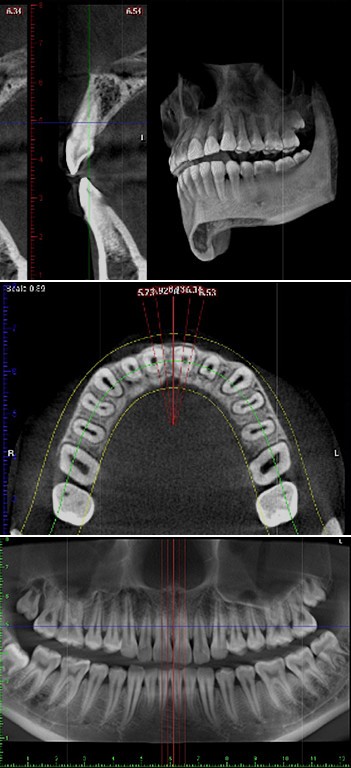

パノラマ(保険適用)、セファロそして歯科用CT撮影を可能としたフィンランド・プランメカ社のProMax 2D/3Dを採用したデジタルX線撮影による診断を行っています。

通常のX線被爆量の70%以上も低減しますので、妊婦の方でも安心して検査していただけます。

フィンランド・プランメカ社のProMax 2D/3Dの導入により、従来の2次元的な平面のみのX線画像では撮影できなかった詳細を、3次元の立体画像で撮影することが可能です。顎の内部構造、顎や歯だけでなく上顎洞(鼻の奥)の形態や粘膜の状態、病巣などを立体的に把握し、正確な診査・診断を可能とするため、インプラントだけでなく、矯正、親知らず、根管治療など、幅広い歯科治療において治療の安全性を高めます。

インプラント治療

埋入する部位の術前の骨の状態(質や厚み、高さ、形態など)を正確に診断し、的確な治療計画をたてることにより、質の高いより安全な治療を実現します。

矯正治療

顎骨の状態から歯の移動の限界が予測できるため、効率の良い治療計画のご提案を実現します。また、現在では矯正用インプラントを固定源として、より正確かつ短期間で矯正治療を行う手法もあり、CT撮影による診断は患者様の選択肢をも拡大します。

歯周病治療

骨の破壊の程度などをより詳細に把握することにより、おおよその歯の寿命の積算が可能となり、非常に予知性の高い治療を実現します。

親知らず

抜歯部位を立体的に把握することにより、神経を引っ掛けてしまう可能性、周囲の炎症の程度、病巣の有無や大きさや位置、埋伏歯の位置なども精密に判断・考慮して治療を行うことができるため、余分な切開や骨の切削などを回避できます。

根管治療

歯根の先端の病巣発見や、治療後の治癒の状態などの正確な把握によって、根の病気の完治を目指しやすくなります。